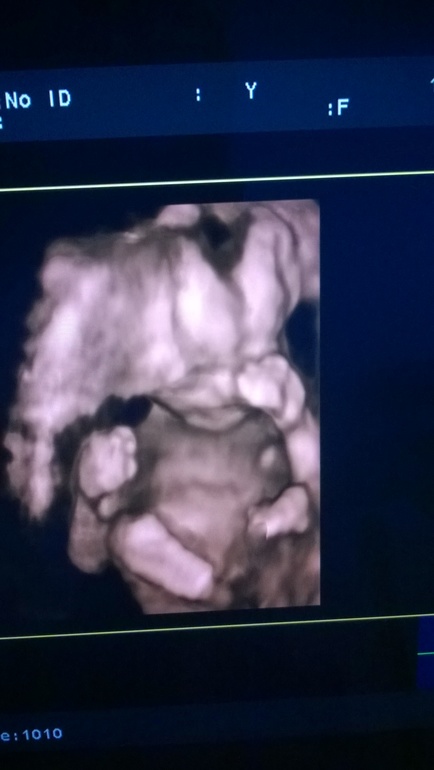

Давно не была, отчитываюсь....были мы на втором скрининге, все у нас отлично, все по плану и рост и вес... даже вот в 3Д показали мне мою крошечку...утвердительно сказали, что девочка, на радостях уже заказаны первые шмоточки в интернете, жду посылочку теперь...

он такой маленький и такой необыкновенный мой малышок!

аж глаза на мокром месте до чего это мило.